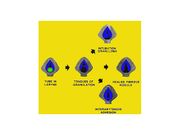

| 08:52, 22 October 2018 | Intub inju.jpg (file) |  |

81 KB | Drtbalu | |